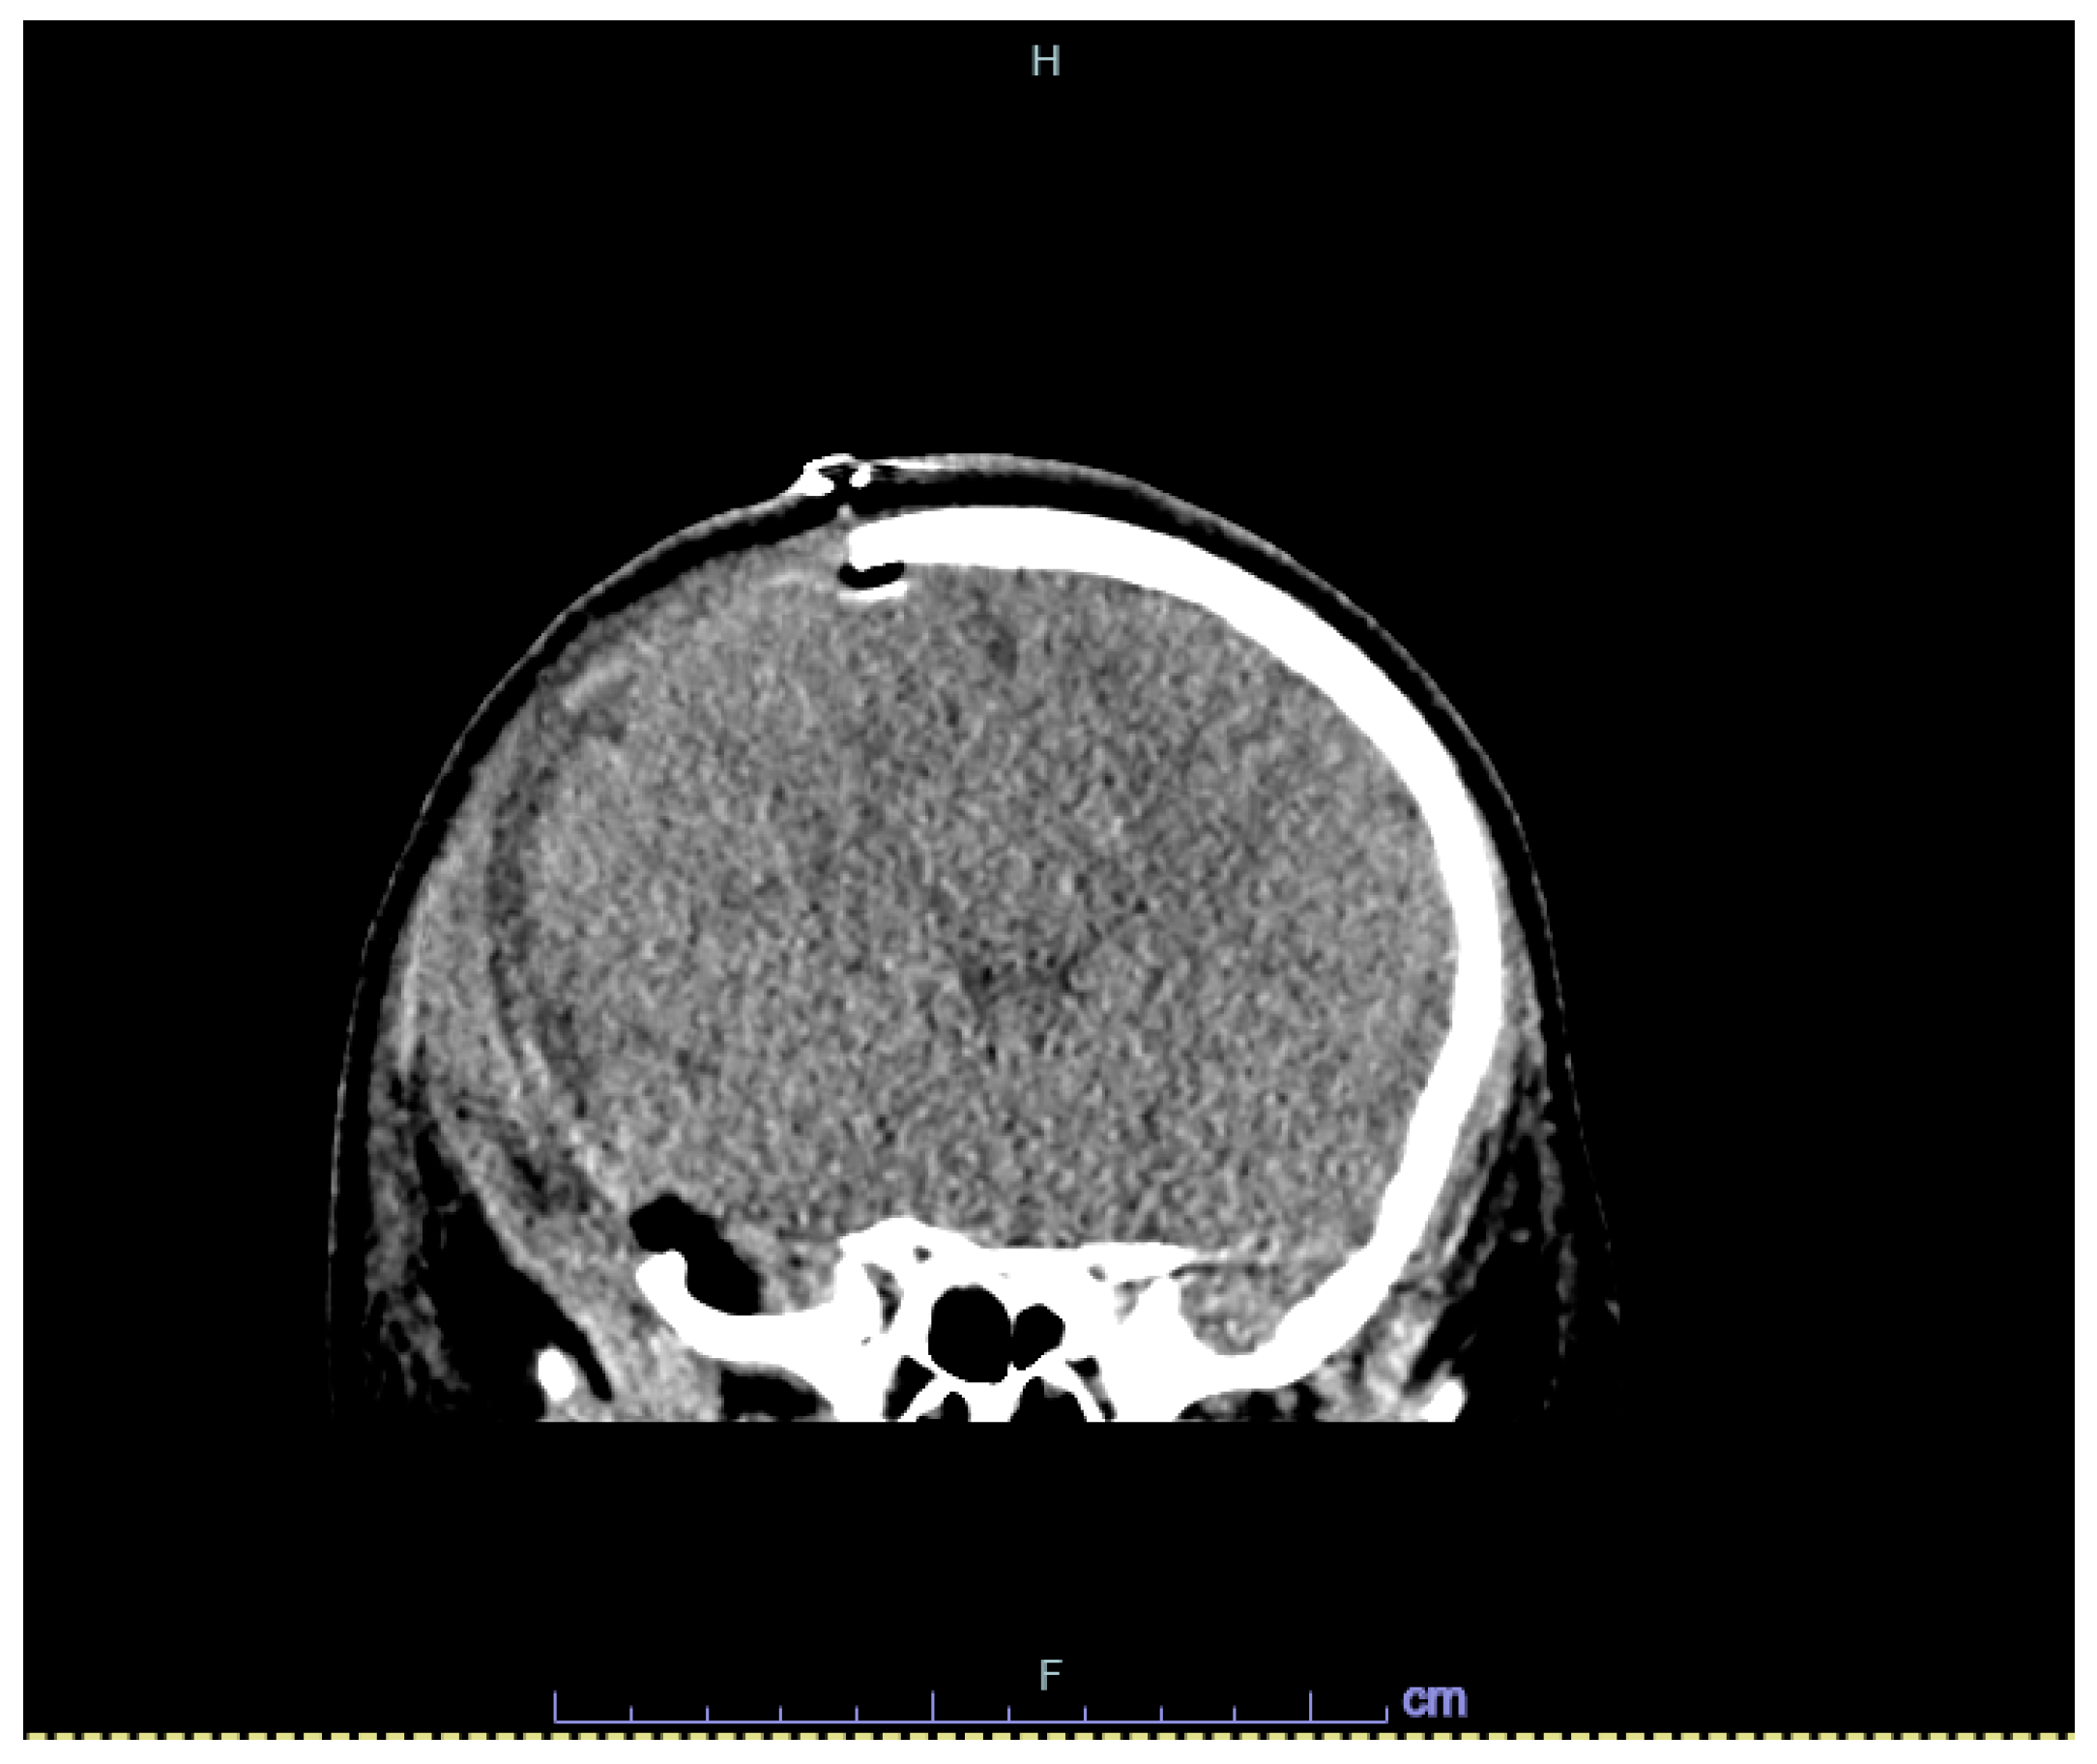

2. Case